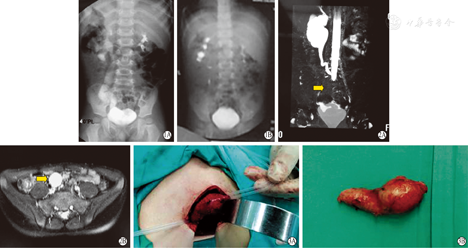

例1 男,6岁。因间断左腰部疼痛1月余,检查发现左肾及输尿管积水(图1)入院,无发热、呕吐、血尿、尿频尿急尿痛等症状。考虑左输尿管远端狭窄,拟行左侧输尿管膀胱再吻合术,术中发现左输尿管下段一1.5 cm×1.5 cm×1.2 cm质硬肿物,局部包膜完整,周围组织未见明显浸润,局部未见肿大淋巴结。距肿物上方约1 cm处离断输尿管,连同肿物一并切除,剩余输尿管与膀胱经黏膜下隧道吻合。

例2 男,10岁,间断腹痛就诊,不伴发热、血尿、呕吐等其他症状,检查发现右侧输尿管远端占位2月入院,B型超声、CT及MRI均提示右输尿管中下段实性占位性病变(图2),行右输尿管下段肿物切除+输尿管端端吻合术,术中见右输尿管中下段肿物大小约5.0 cm×1.8 cm×2.0 cm,质硬,包膜完整,与周围组织分界清(图3)。

2例患儿术后顺利恢复出院,病理诊断均为输尿管炎性肌纤维母细胞瘤,未行放化疗及其他治疗。目前例1随访至术后54个月,肾输尿管积水较前明显减轻(图1、图2);例2随访至术后24个月,泌尿系超声提示肾输尿管积水较前明显减轻,2例均未见肿瘤复发及转移。